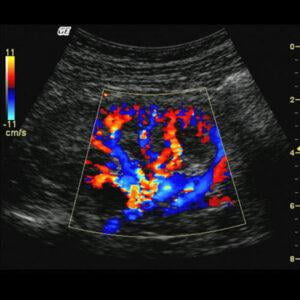

“Health is wealth” there is no denying this saying. With the right health, you can go about your daily life with greater strength, vitality, and agility, maintaining your health is also a very necessary step. Taking the necessary tests is also very important to assess whether or not you are facing issues in your body internally. An ultrasound test can help your doctors a great deal in understanding the internal organs and if there is any flaw in the internal structural functioning of your body. Semwal Diagnostics, one of the leading ultrasound facilities offers you the best services. Colour Doppler Test is one such ultrasound test technique that helps doctors to estimate the blood flow in your veins and arteries.

A Colour Doppler Ultrasound test is a non-invasive ultrasound technique. It gives the doctors a way to see what is going on inside your body without any injections or X-rays making it a no-pain procedure.

It is used to diagnose any irregularity in hemodynamics or in simpler terms it can detect the blood flow in major arteries and veins of various body parts such as the neck, arms, and legs while also detecting if there are any blockages in the same that can cause further harm. A Colour Doppler Test essentially turns sound waves into images so it helps in creating an image of the blood flow that cannot be created with the help of a regular ultrasound.

Colour Doppler shows the speed and direction of the blood flow. The sound waves that are converted into the image on the computer screen are shown in different colours.